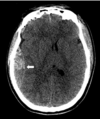

Describe

traumatic epidural hematoma